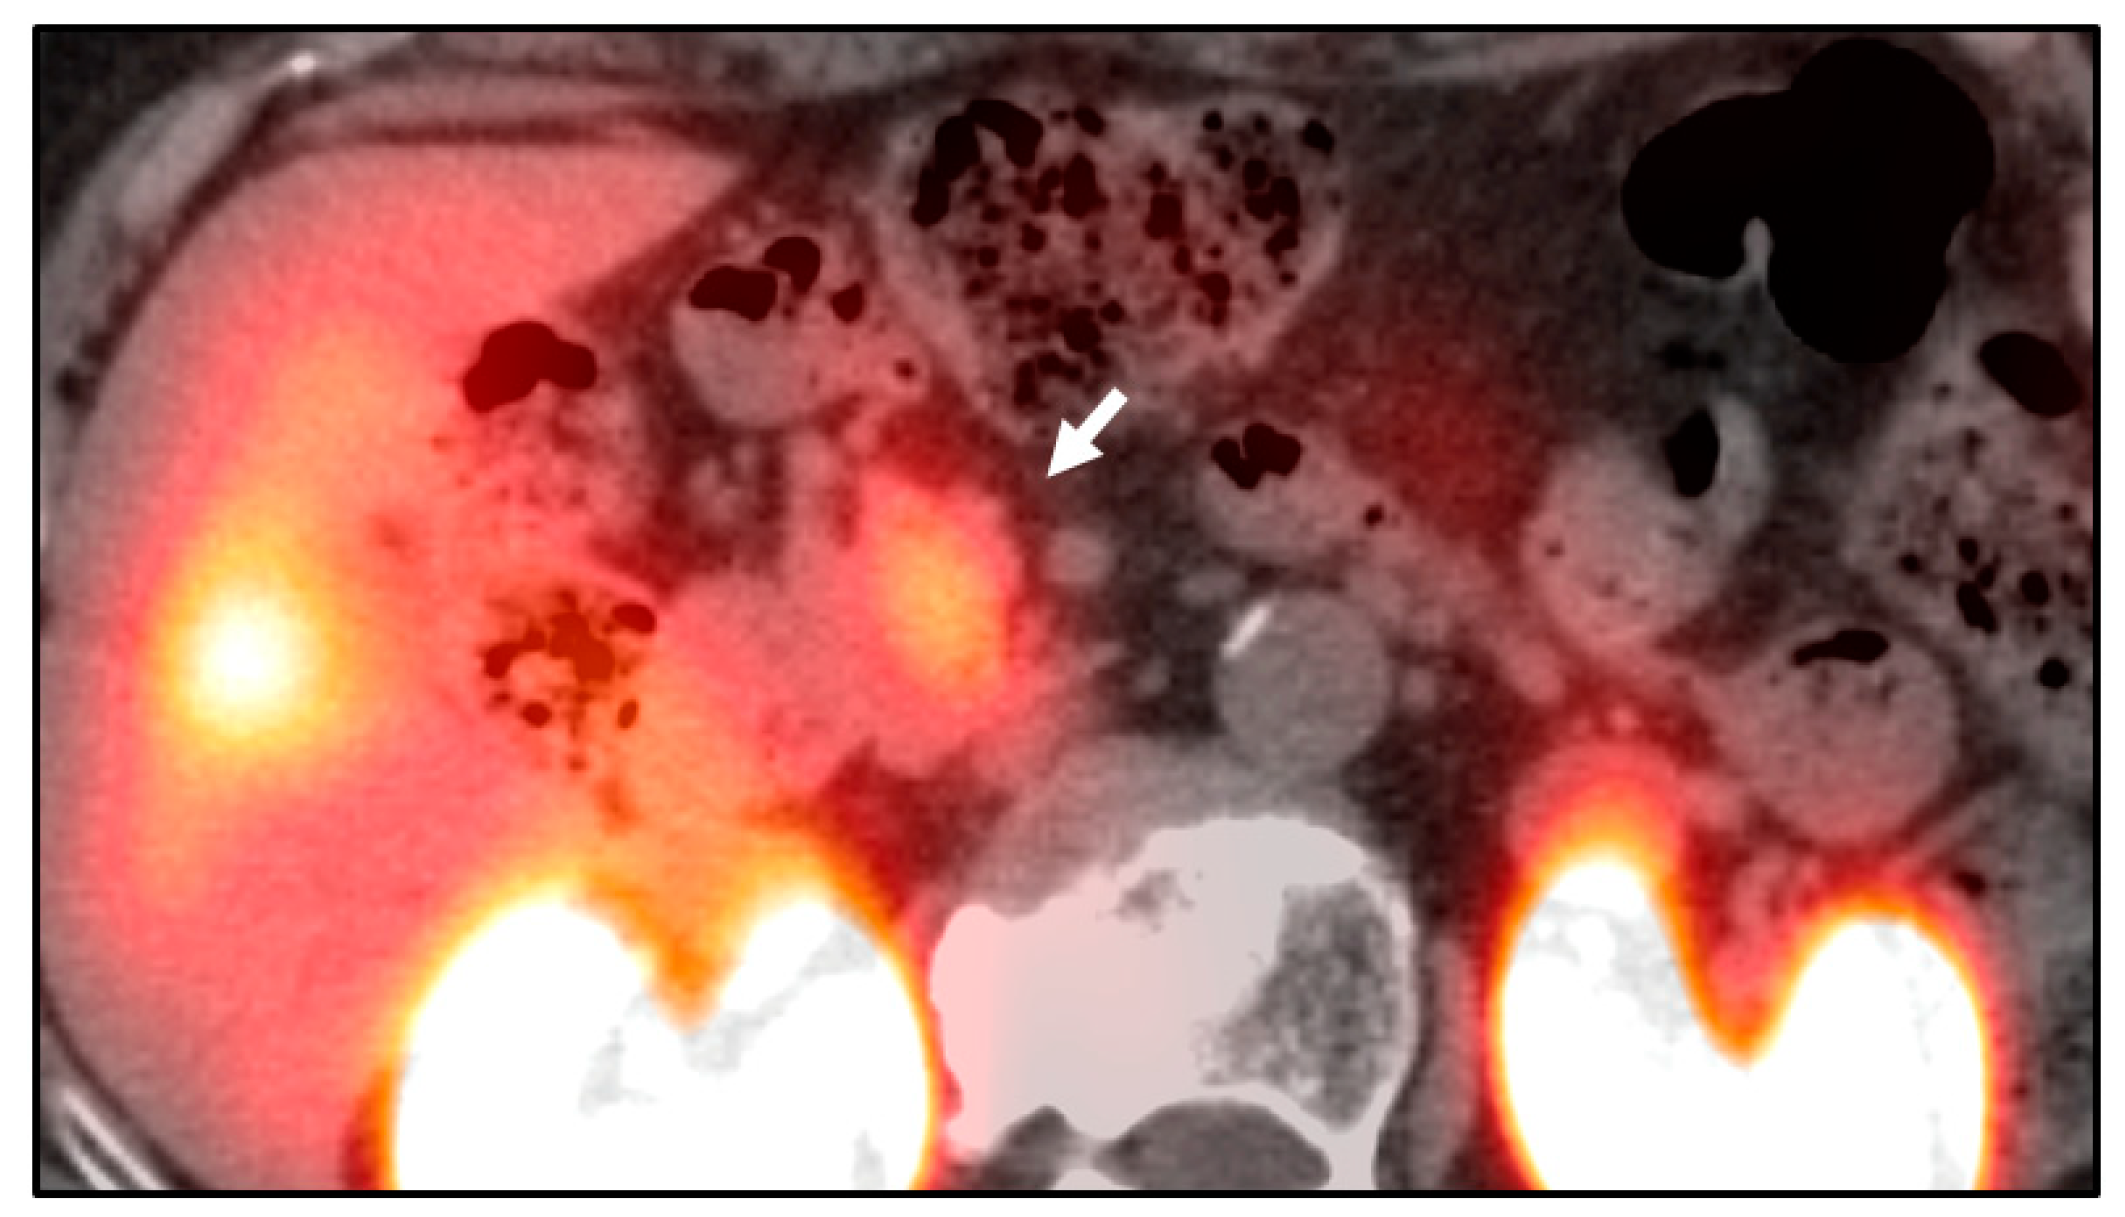

- Nockel, P.; Babic, B.; Millo, C.; Herscovitch, P.; Patel, D.; Nilubol, N.; Sadowski, S.M.; Cochran, C.; Gorden, P.; Kebebew, E. Localization of Insulinoma Using 68Ga-DOTATATE PET/CT Scan. J. Clin. Endocrinol. Metab. 2017, 102, 195–199. [Google Scholar] [CrossRef] [PubMed]

- Sharma, P.; Arora, S.; Karunanithi, S.; Khadgawat, R.; Durgapal, P.; Sharma, R.; Kandasamy, D.; Bal, C.; Kumar, R. Somatostatin receptor based PET/CT imaging with 68Ga-DOTA-Nal3-octreotide for localization of clinically and biochemically suspected insulinoma. Q. J. Nucl. Med. Mol. Imaging 2016, 60, 69–76. [Google Scholar] [PubMed]

- Antwi, K.; Fani, M.; Heye, T.; Nicolas, G.; Rottenburger, C.; Kaul, F.; Merkle, E.; Zech, C.J.; Boll, D.; Vogt, D.R.; et al. Comparison of glucagon-like peptide-1 receptor (GLP-1R) PET/CT, SPECT/CT and 3T MRI for the localisation of occult insulinomas: Evaluation of diagnostic accuracy in a prospective crossover imaging study. Eur. J. Nucl. Med. Mol. Imaging 2018, 45, 2318–2327. [Google Scholar] [CrossRef]